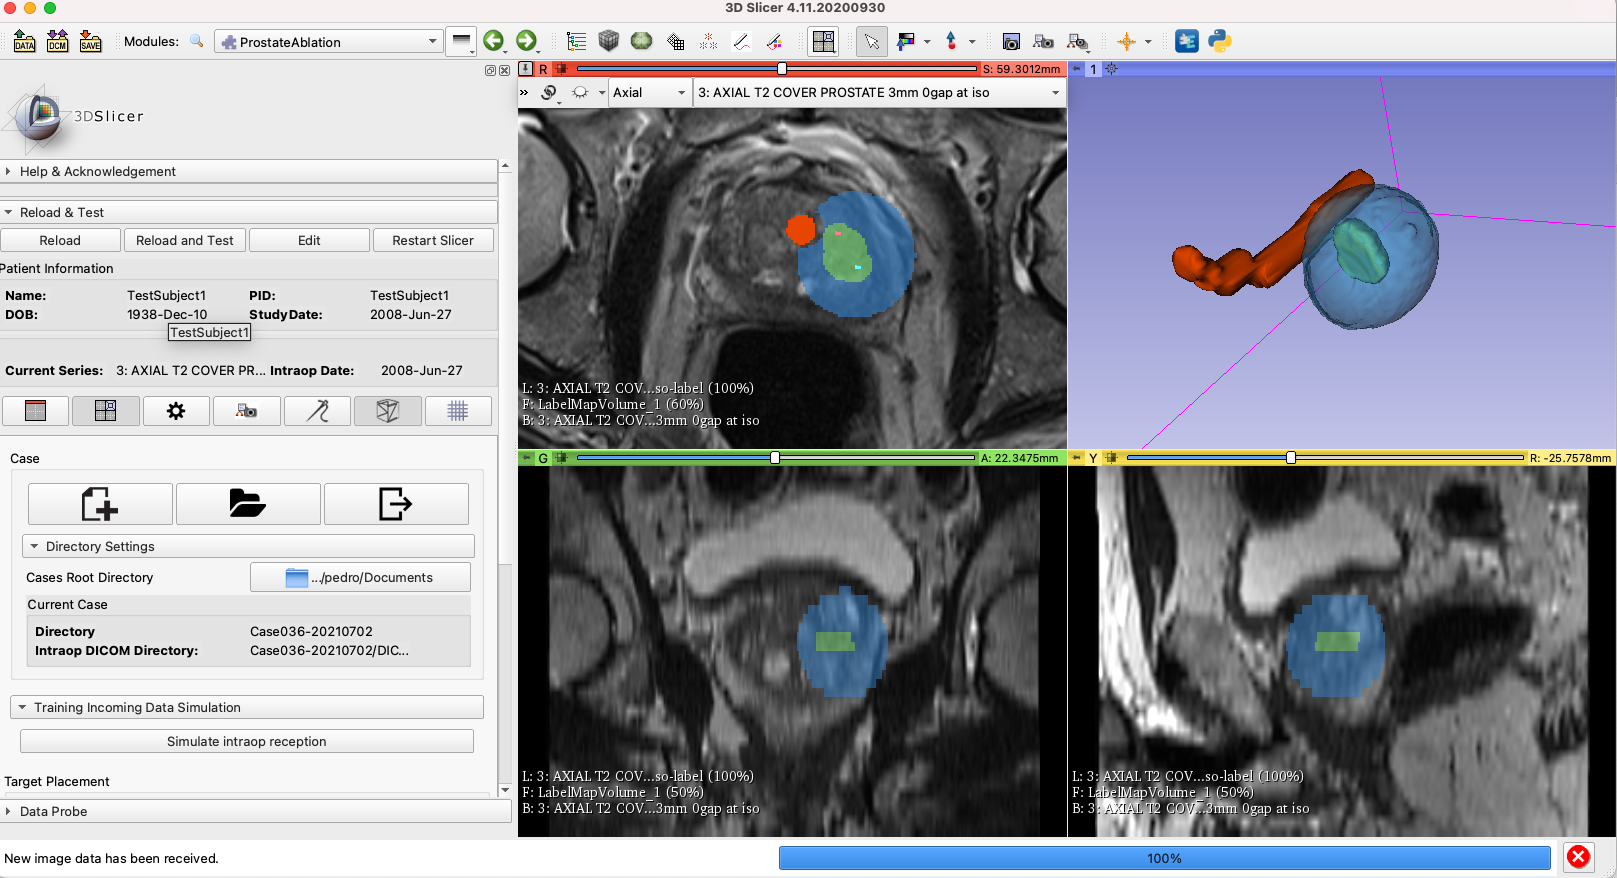

Figure 3: Integration of the iceball estimation and the ProstateAblation module. the ablation target is marked in green, while the estimated iceball is in blue.

One of the advantages of the current approach is the prediction and the vizualization of the ablation margins in 3D, However, we still need to discuss the best way to vizualize the prediction and planning results. We should meet the Dr. Tuncali soon to get his input.